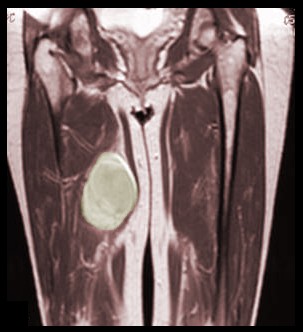

Patient with a large sarcoma in the right anterior thigh: CT here, MRI here and here, PET after neoadjuvant chemotherapy here and here

MRI Scan